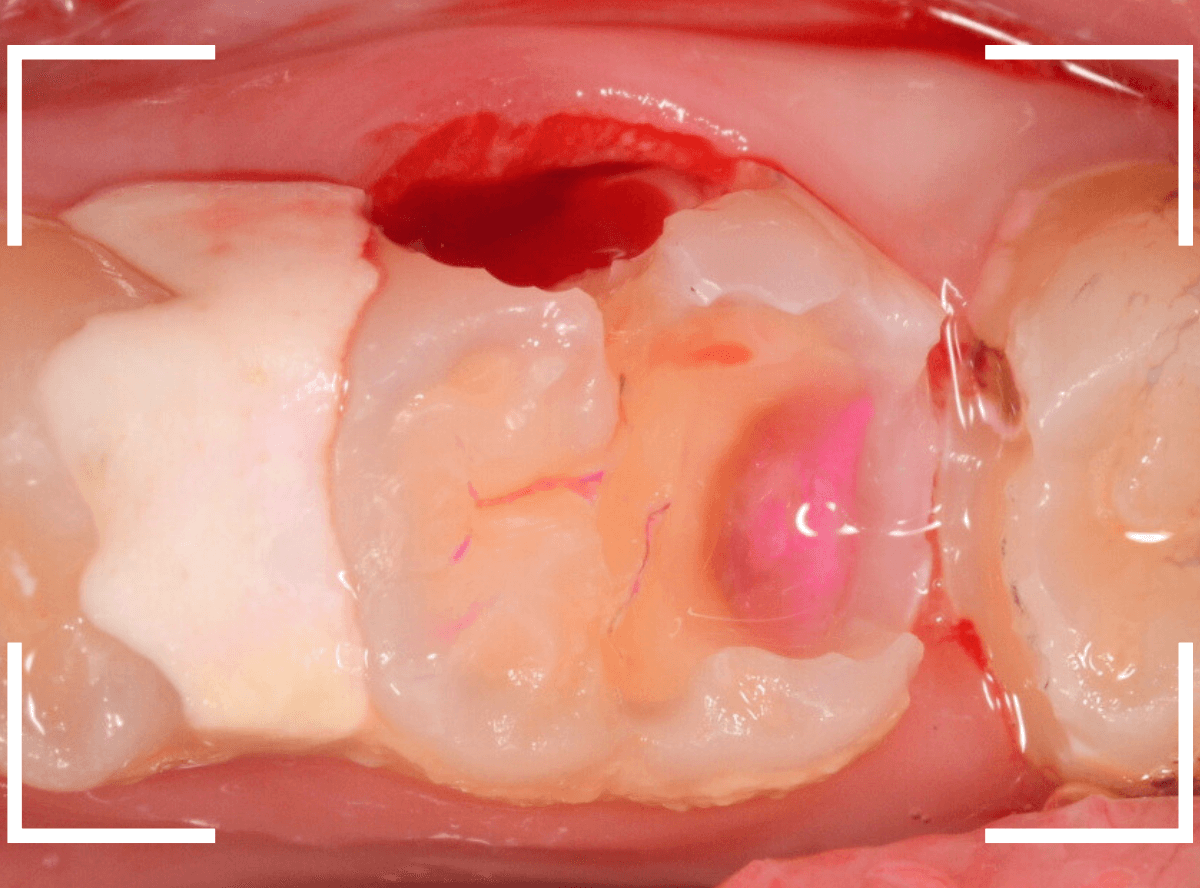

「下の奥歯が痛む」という訴えで来院された患者さんのケースです。

目視でも、手前の奥歯がかけていて、中で虫歯が広がってるであろうことは予想できます。

ピンセットで歯を叩いてみても、手前の奥歯が痛むようです。

レントゲン写真で確認します。

青い線が神経、赤い線が虫歯の範囲です。

奥歯の方がより深い虫歯に見えますが、再度打診で確認したところ、やはり手前の奥歯が痛むそうです。

状況から、まず手前の奥歯から治療となりました。

麻酔をして、手前の奥歯のレジンを慎重に外します。

前に虫歯の治療をした時点で、神経スレスレの状態でしたので、削りすぎないように慎重にレジンを外さなければいけません。

レジンを外して、う蝕検知液で確認します。

レジンの中で虫歯が進行していたのがわかります。

慎重に全ての虫歯を除去しました。

何とか、神経が露出せずに済んでいます。

お薬をつめて、セメントで蓋をして経過観察します。